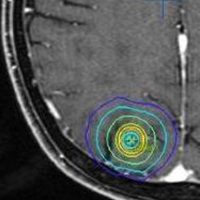

放射線外科 SRS の治療計画です。左側のとても小さな脳転移にたいして,中心線量25グレイ,辺縁線量20グレイの計画です。黄色の線より外にはほとんど放射線が入らない治療です。でも周辺脳が全く被曝しないわけではありません。